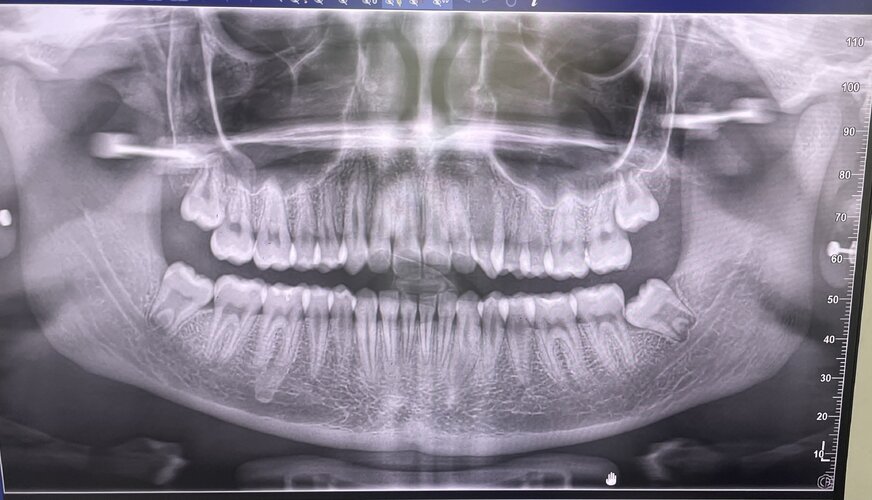

Expansion. Here is my xray what do you think?

• IMG_8681.jpeg

IMG_8681.jpeg